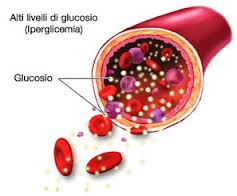

Secondo la scoperta, il diabete di tipo 2, fino ad ora considerata una malattia metabolica, è più vicino al tipo 1 diabete, condizione in cui il sistema immunitario attacca e distrugge le cellule che producono insulina nel pancreas. Il diabete di tipo 2 si verifica quando i tessuti del corpo gradualmente diventano sempre resistenti al’ insulina, l’ormone che trasporta il glucosio alle cellule dove viene convertito in energia. Non sappiamo perchè i tessuti diventano resistenti all’insulina nel diabete di tipo 2, ma sappiamo che questa condizione è legata all’obesità. I ricercatori hanno iniziato a pensare che le cellule immunitarie, comprese le cellule T (coinvolte principalmente nella risposta immunitaria cellulo-mediata) e le cellule B ( coinvolte principalmente nella risposta anticorpale), possono causare infiammazione nel tessuto adiposo che circonda e protegge gli organi interni, provocando il caos nel tessuto adiposo.

Studiando la reazione più da vicino, i ricercatori hanno trovato essa coinvolge non solo i macrofagi, ma anche le cellule T e le cellule B, che gradualmente inibiscono la capacità delle restanti cellule di grasso di rispondere all’insulina. In questo modo gli acidi grassi di penetrano nel sangue e quando i loro livelli sono troppo elevati, si possono sviluppare condizioni come malattia fegato grasso, colesterolo alto , pressione alta e ancora di più, la resistenza del corpo all’ insulina.

Nella fase finale dello studio, i ricercatori hanno testato l’ effetto dell’anticorpo anti-CD20 approvato dalla FDA Rituximab, nei topi alimentati con dieta ad alta percentuale di grassi o dieta ipercalorica, per 6 settimane. Essi hanno dimostrato che l’anti-CD20 attacca le cellule B mature e le distrugge. Dopo un periodo iniziale di trattamento, i topi hanno migliorato la loro capacità di metabolizzare il glucosio e il loro livelli di insulina a digiuno sono saliti: Tuttavia, dopo 40 giorni, che è il tempo di durata del trattamento, quando nuove cellule B si sono riformate, i topi hanno cominciato a sviluppare nuovamente l’insulino-resistenza.